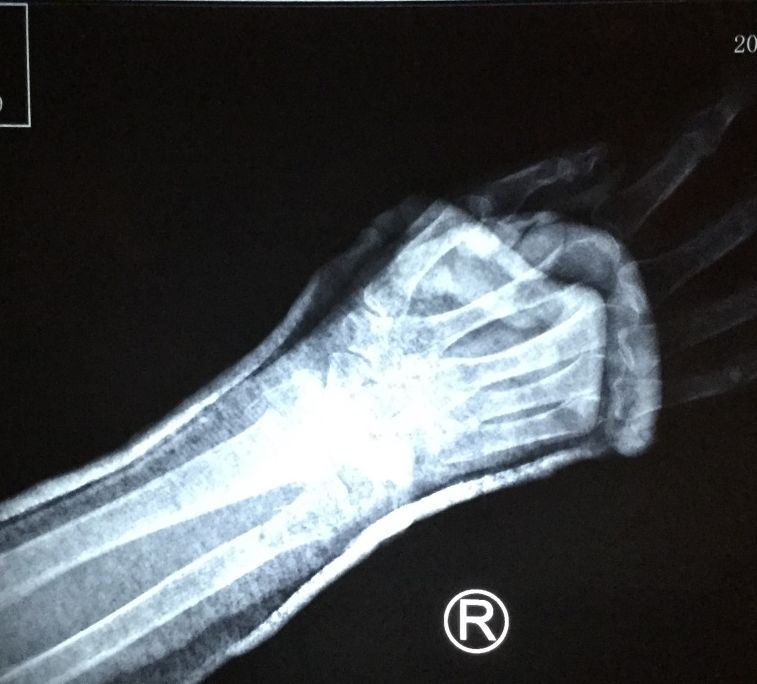

【明慧网二零一九年二月二十四日】〖大陆来稿〗二零一九年一月二十八日上午十时许,现年八十三周岁的北京市民善珍奶奶(化名)在家中客厅穿衣时,不慎摔倒,右手腕部戳在餐桌一角,很疼痛。当时家人将老人送至就近医院检查,拍片结果显示如图1。检查报告单中描述为:右侧桡骨、尺骨远段可见骨质断裂,骨折端掌侧成角,远折端背侧移位(图2)。

'图1'

图1